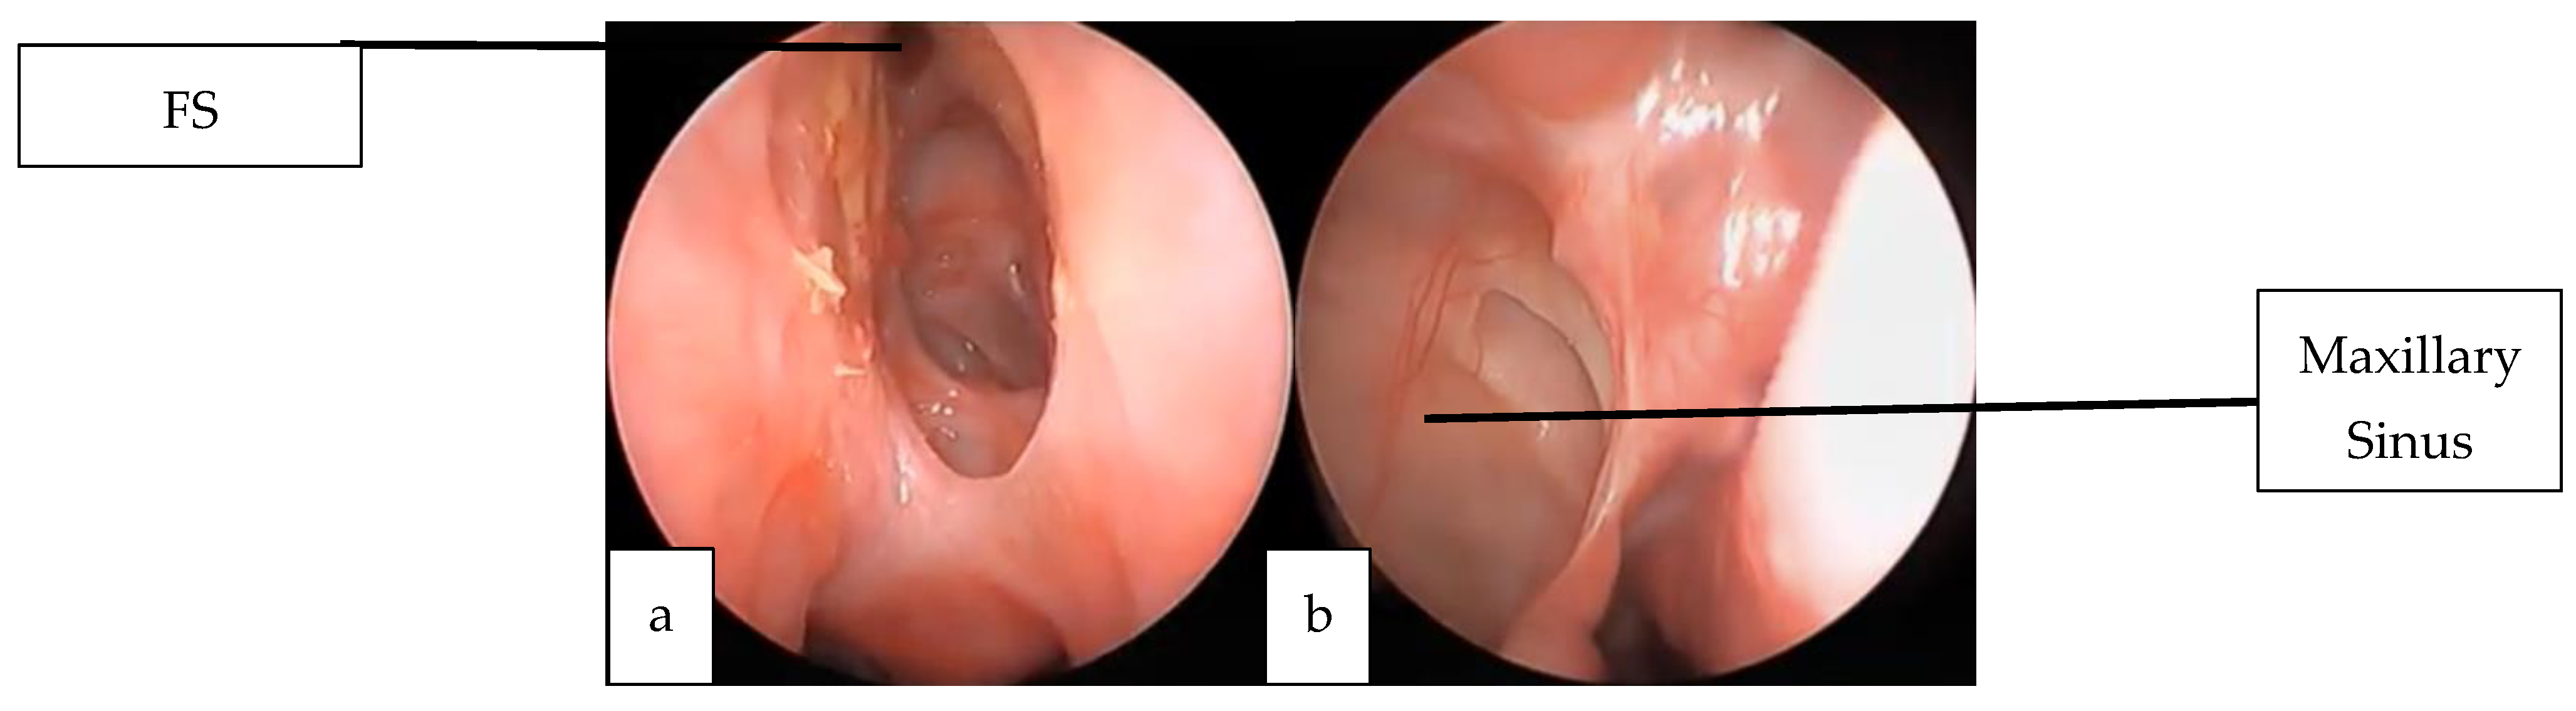

2.1. Case 1

2.2. Case 2